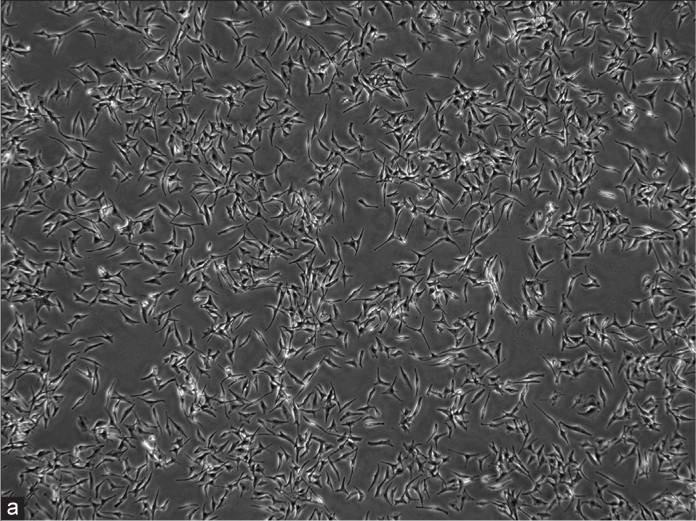

They divided melanocytes into three groups: blank (melanocytes), Group 1 (melanocytes with fibroblast-derived exosomes) and Group 2 (melanocytes with keratinocyte-derived exosomes). The exosomes were labeled with PKH67 dye. Bright green particles were seen in Group 2 melanocytes, located in the cell bodies and dendrites (Fig. 3a and b), but not in Group 1. After 48 hours, no significant difference was noted in cell density between the blank group and Group 1(Fig. 3c), but Group 2 melanocytes proliferated rapidly and were densely packed (Fig. 3c). All groups showed typical melanocyte morphology. The blank group and Group 1 had similar bipolar or tripolar dendrites (Fig. 3c). In contrast, Group 2 showed multiple dendrites clustering together, unlike the others (Fig. 3c). Tyrosinase activity was measured, showing that keratinocyte exosomes significantly increased activity compared to the blank group and Group 1. No difference was found between Group 1 and the blank group (Fig. 4a). Analyses of melanin content showed that keratinocyte exosomes significantly increased melanin compared with both the blank and Group 1 groups (although no difference was observed between Group 1 and the blank group) (Fig. 4b). Together, keratinocyte-derived exosomes were digested by melanocytes that co-cultured with them and facilitated their growth, tyrosinase activity and melanin production. Yet fibroblast exosomes did not act the same way on melanocytes.

Fig. 3. (a-b) Characteristics of the internalization of exosomes in melanocytes. (c) Morphological observations of melanocytes (Shi HX, Zhang RZ, et al., 2022).